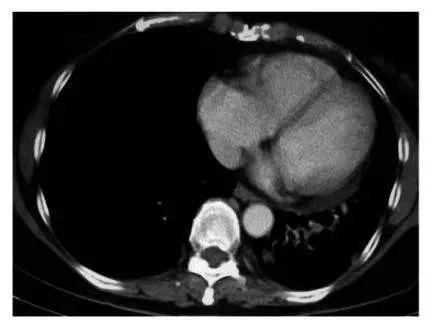

美国晚期肺癌患者慕名前往古巴接受治疗,经疫苗治疗几个月后,肺部影像检查发现肿瘤竟然已经缩小了90%,完全超出了所有人的想象,并且治疗过程完全没有出现化疗时的任何副作用。

癌细胞肿胀坏死的过程

A 治疗前血清 B-D 三个免疫治疗患者的血清